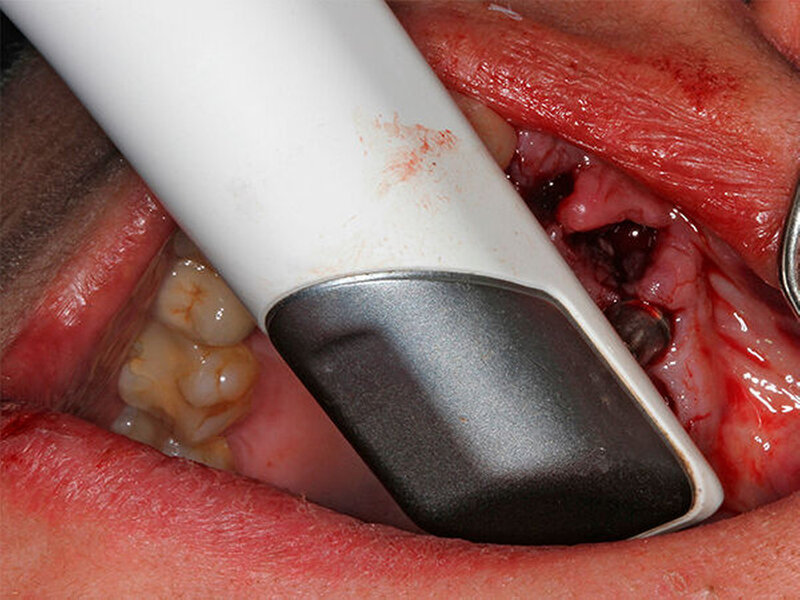

Schnutenhaus:

Wir haben extrahiert, dann die Implantate inseriert, direkt nach der Implantation die Scanbodys aufgesetzt, den optischen Abdruck genommen und das Langzeitprovisorium aus PMMA verschraubt. Dass die Innenverbindung immer die gleiche ist, hilft dabei sehr. Eine Prothetik passt tatsächlich auf alle Implantate.